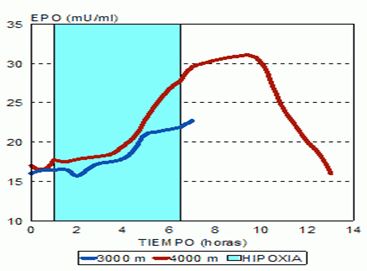

En el contexto deportivo, los estímulos de hipoxia intermitente pasiva o activa, aumentan los niveles de EPO, según la carga hipóxica más o menos. Normalmente después de exposiciones hipóxicas de 1-2 horas, inducen secreciones máximas de EPO a las 6-10 horas y luego los valores de EPO caen en picada.

Figura 6. Evolución de los niveles de EPO según las altitudes simuladas mediante estímulos de hipoxia intermitente normobárica (www.biolaster.com)